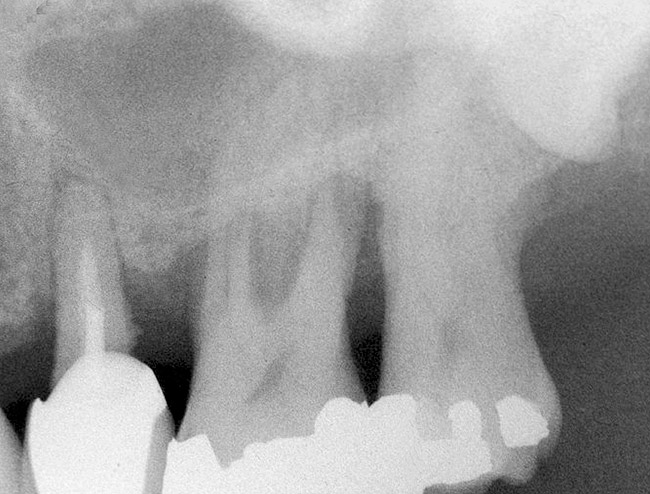

The technique is based on the use of specially designed drills and osteotomes. With this technique the regeneration of a substantial amount of new bone is a predictable outcome only in narrow sinus cavities. During presurgical planning bucco palatal sinus width should be regarded as a crucial parameter when. Immediate implant and endoscope guided sinus floor elevation through a transcrestal approach by using prf as the only grafting material is viable in periapical infected sites with a rbh of less than 1 mm.

Number of times cited according to crossref. Transcrestal sinus floor elevation has no negative effect on the long term implant survival. Membrane perforation or negligible bone height however reduces the probability of 10 year survival.